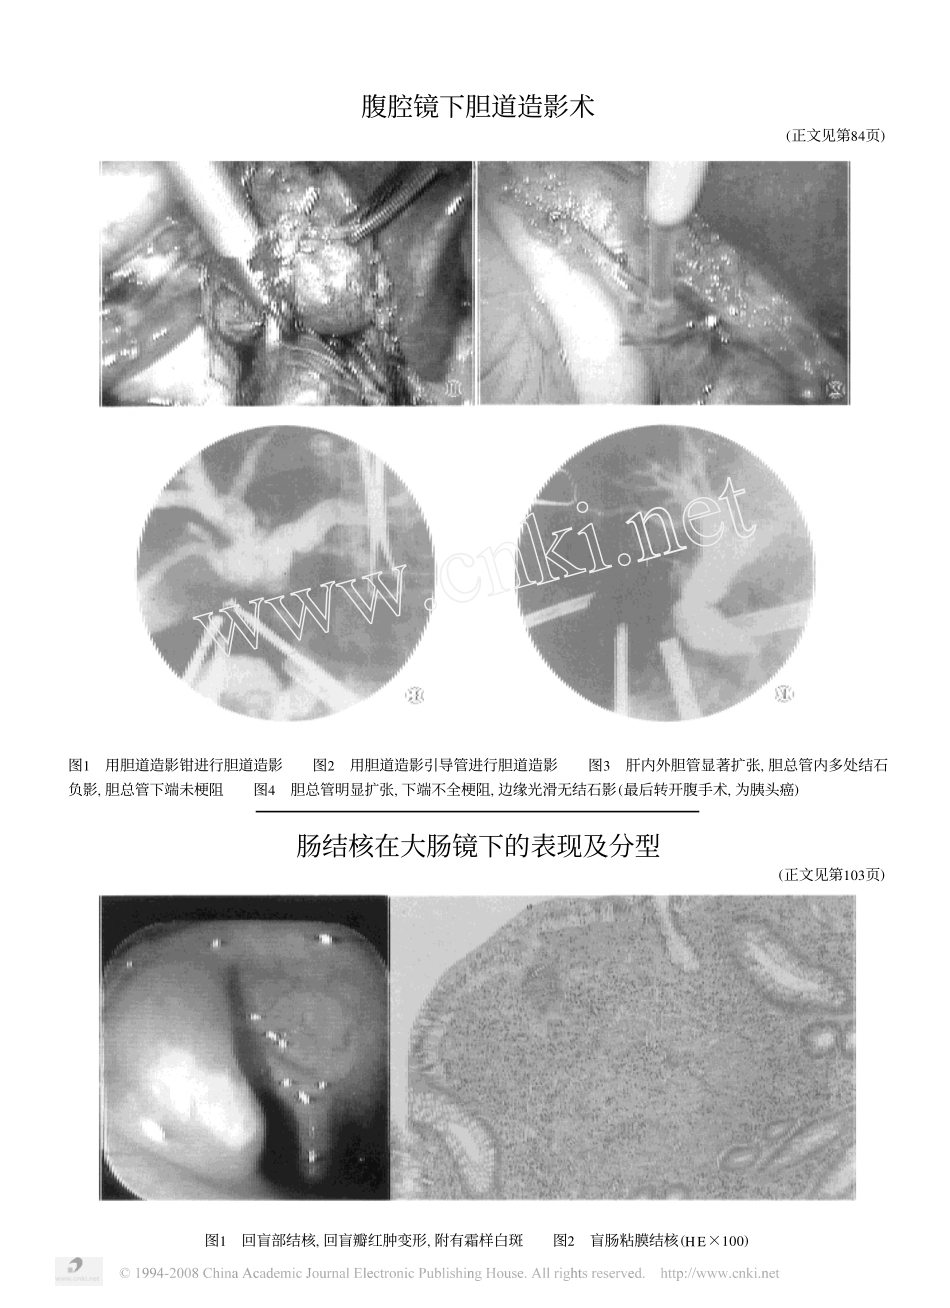

作者单位:510282广州,第一军医大学珠江医院肠结核在大肠镜下的表现及分型宋卫生杨冬华余建林郭琳琅李立平摘要为使肠结核肠镜下分型更合理,文章总结了39例肠结核在大肠镜下的表现,在溃疡型、增生型和混合型(溃疡增生型)的基础上提出了炎症型。炎症型在肠镜下的表现是粘膜充血、水肿、质脆,血管纹模糊,呈点状或片状糜烂,附黄白色粘液渗出物或霜样白苔,无溃疡和增生性表现。活检病理检查示粘膜结核。炎症型是肠结核的早期病变,活检成功率高。讨论认为炎症型符合肠结核的病理变化规律,是客观存在的,重视炎症型改变可使肠结核在肠镜下获得较早期诊断。关键词肠结核大肠镜表现分型COLONOSCOPICFINDINGSANDTYPINGOFINTESTINALTUBERCULOSISSongWeisheng,YangDonghua,YuJianlin,etal.DepartmentofGastroenterology,ZhujiangHospitaltheFirstMilitaryMedicalUniversity,Guangzhou510282AbstractThispaperpresentsupthecolonoscopicfindingsof39provencasesofintestinaltubercu2losis,21females,and18males,themeanagebeing4017years(ranging9to71years).Inflammatorytypeisproposed.Thecolonoscopicfindingsofthisinflamatorytypeincludebyperemia,edemaofinvolvedmu2cosawithafriableanderosiveappearanceoftheinterveningmucosa,coveredbyalayeroffibrino2puru2lentexudateorfrostywhitemucus.Colonoscopyfailedtoulcerationorhypertrophy,howeverbiopsycouldprovemucosaltuberculosis.Astheinflamatorytypebeingtheearlystageofintestinaltuberculosiswithlesionslocalizedtomucosaonly,thediagnosisbybiopsyisquitecertain.Itisconsideredthattheproposalofinflamatorytypebytheauthorswouldbethebasisofestablishinganearlydiagnosisofin2testinaltuberculosisundercolonoscope.KeywordsIntestinaltuberculosisColonoscopeFindingsTpying肠结核在我国比西方国家多见。大肠镜是目前诊断肠结核较有效的方法。本文总结了39例肠结核肠镜下的表现,并对其分型作了探讨。临床资料111983年1月至1995年12月本院大肠镜检查8741人,诊断肠结核39例,其中经活检病理证实12例,手术证实3例,抗结核治疗后肠镜复查证实24例。男18例,女21例,年龄9~71岁,平均4017岁。住院26例,门诊13例。肠镜检查2~7次不等。病程最短3天,最长31个月。21临床症状从资料完整的26例住院患者收集。腹痛23例,占8815%,多为轻到中度的阵发性腹痛;腹泻15例,5717%,以每天2~4次糊状便或烂便多见,并有2例血例;合并肠外结核14例,占5318%;尚有消瘦、乏力、包块等。发热者近半数,多在38℃左右;血沉增块21例,达8018%。31病变部位,本组1例升结肠结核使肠腔狭窄,不能进镜达回盲部。到达回盲部的38例中37例均见回盲部病变,占9714%。回盲瓣病变34例,占8915%。进入回肠末端13例,9例发现病变,占6912%。病变侵及升结肠14例,占3519%,侵及横结肠4例,占1013%,侵及乙状结肠5例,占1218%,侵及直肠6例,占1514%,其中4例全大肠各段均有病变,呈节段性跳跃式分布。肠镜下表现及分型11炎症型2例,占511%。表现为粘膜充血、—301—中华消化内镜杂志1997年4月第14卷第2期水肿、血管纹理模糊,粘膜质脆,粘液渗出物多,亦可见到点状或片状糜烂灶,表面附黄白色粘稠渗出物或霜样白苔(见附图页图1)。其中1例病变局限于回肠末端,1例病变侵及盲肠、升结肠始段及回盲瓣。2例均经活检病理学证实为粘膜结核(附图页图2)。此型属于肠结核病变早期。21溃疡型13例,占3313%。溃疡多不规则,数量、大小、深浅不一,小者似阿夫它样溃疡密集散在,大者1~3cm不等,呈椭圆形或类圆形,横形走向,边缘不规整,潜行性,呈堤状隆起或放射状,可充血水肿,亦可无明显炎症反应,底部覆黄白色苔,部分可见肉芽组织生长。溃疡可单发或多发,在回肠末端、回盲瓣、盲肠及大肠各段均可见到。31增生型9例,占2311%。肠镜见病变处呈结节状红肿隆起,皱襞增厚,结肠袋变浅或消失,肠腔环形狭窄,僵硬。亦可见到类似铺路石样改变,凹陷处粘膜糜烂渗出,多数并有宽基或亚蒂息肉状肿物,可呈癌样溃烂肿物,使肠腔狭窄肠镜不能通过。本组1例误诊为升结肠癌而经手术诊断为结核。41混合型(溃疡增生型)15例,占3815%。此型溃疡和增...